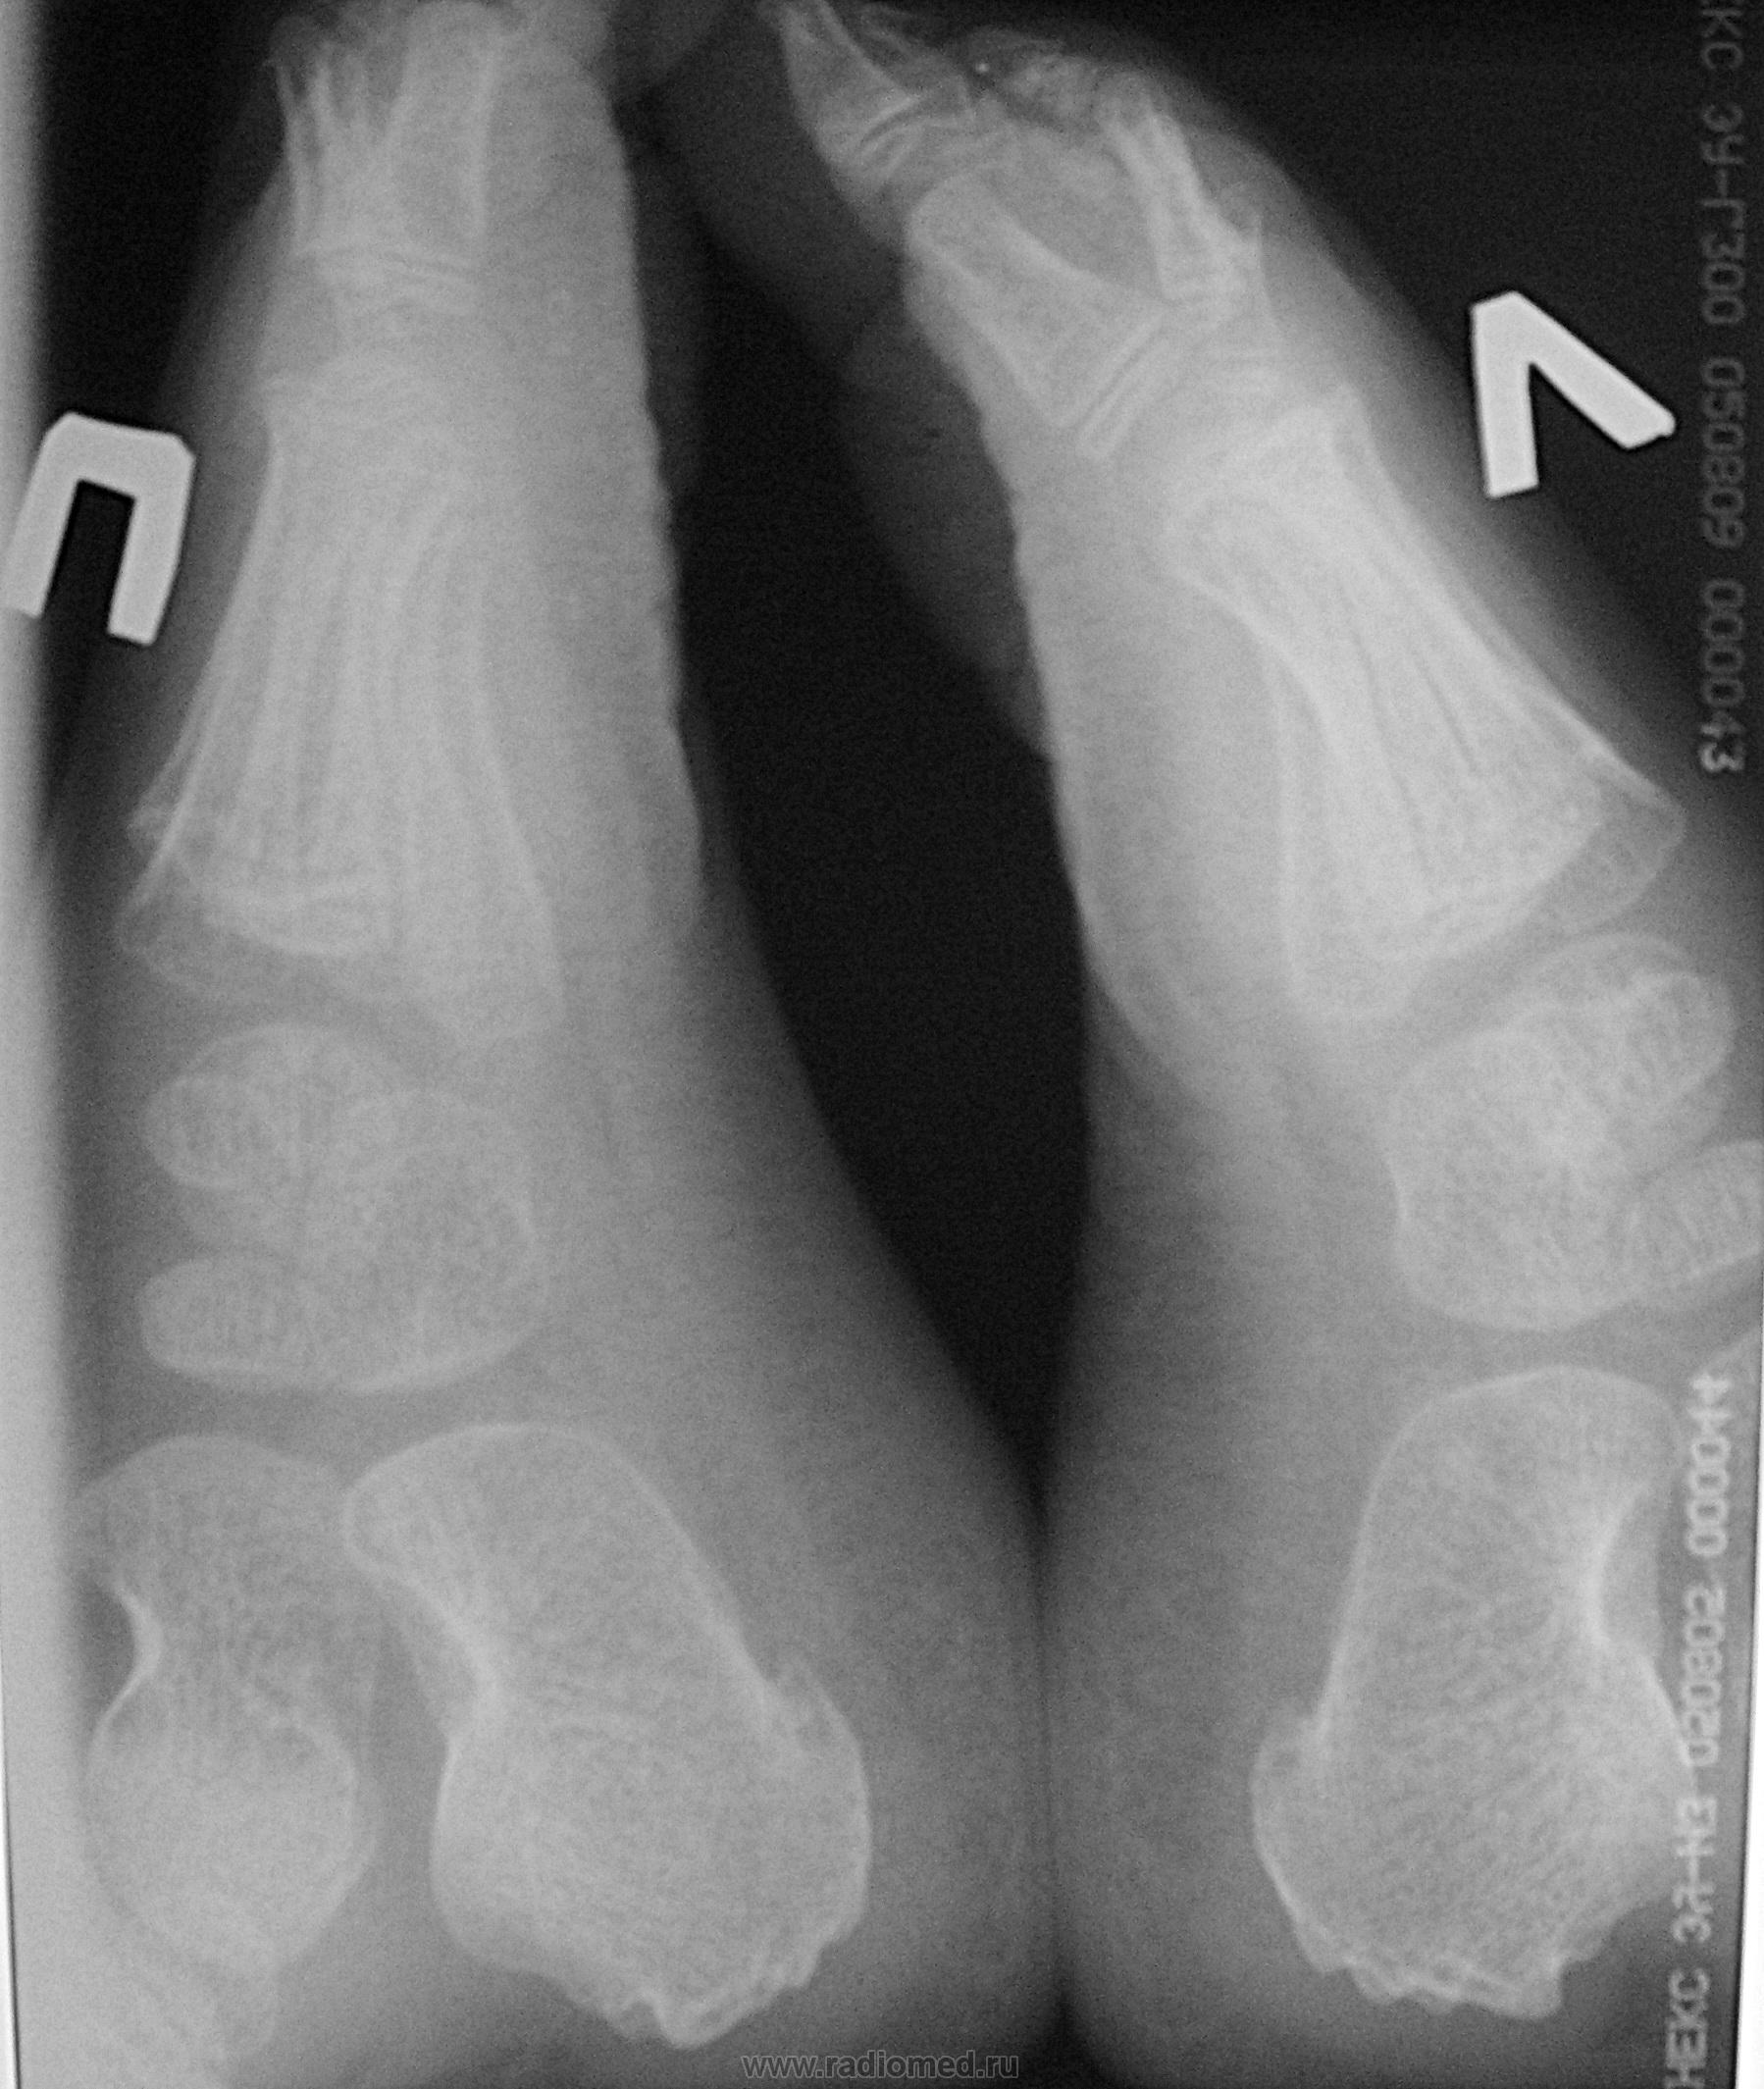

Пол пациента: Женский пол Тип патологии: Травма Область исследования: Скелетно-мышечная система Методы исследования: Rg Девочка 9 лет обратилась с жалобами на боль в пяточной кости после прыжка(худ. гимнастика). ID:13842 Пт, 13/05/2011 - 05:09 #1 10dent I.A. Не на сайте Был на сайте: 11 лет 4 месяцев назад Зарегистрирован: 25.04.2011 - 15:53 Публикации: 47 - Р-признаков переломов не отмечается - Любопытны "шпоры" обеих пяточных костей, и есть ли у нее плоскостопие? ...я мало видел, еще меньше знаю...

- Р-признаков переломов не отмечается

- Любопытны "шпоры" обеих пяточных костей, и есть ли у нее плоскостопие?